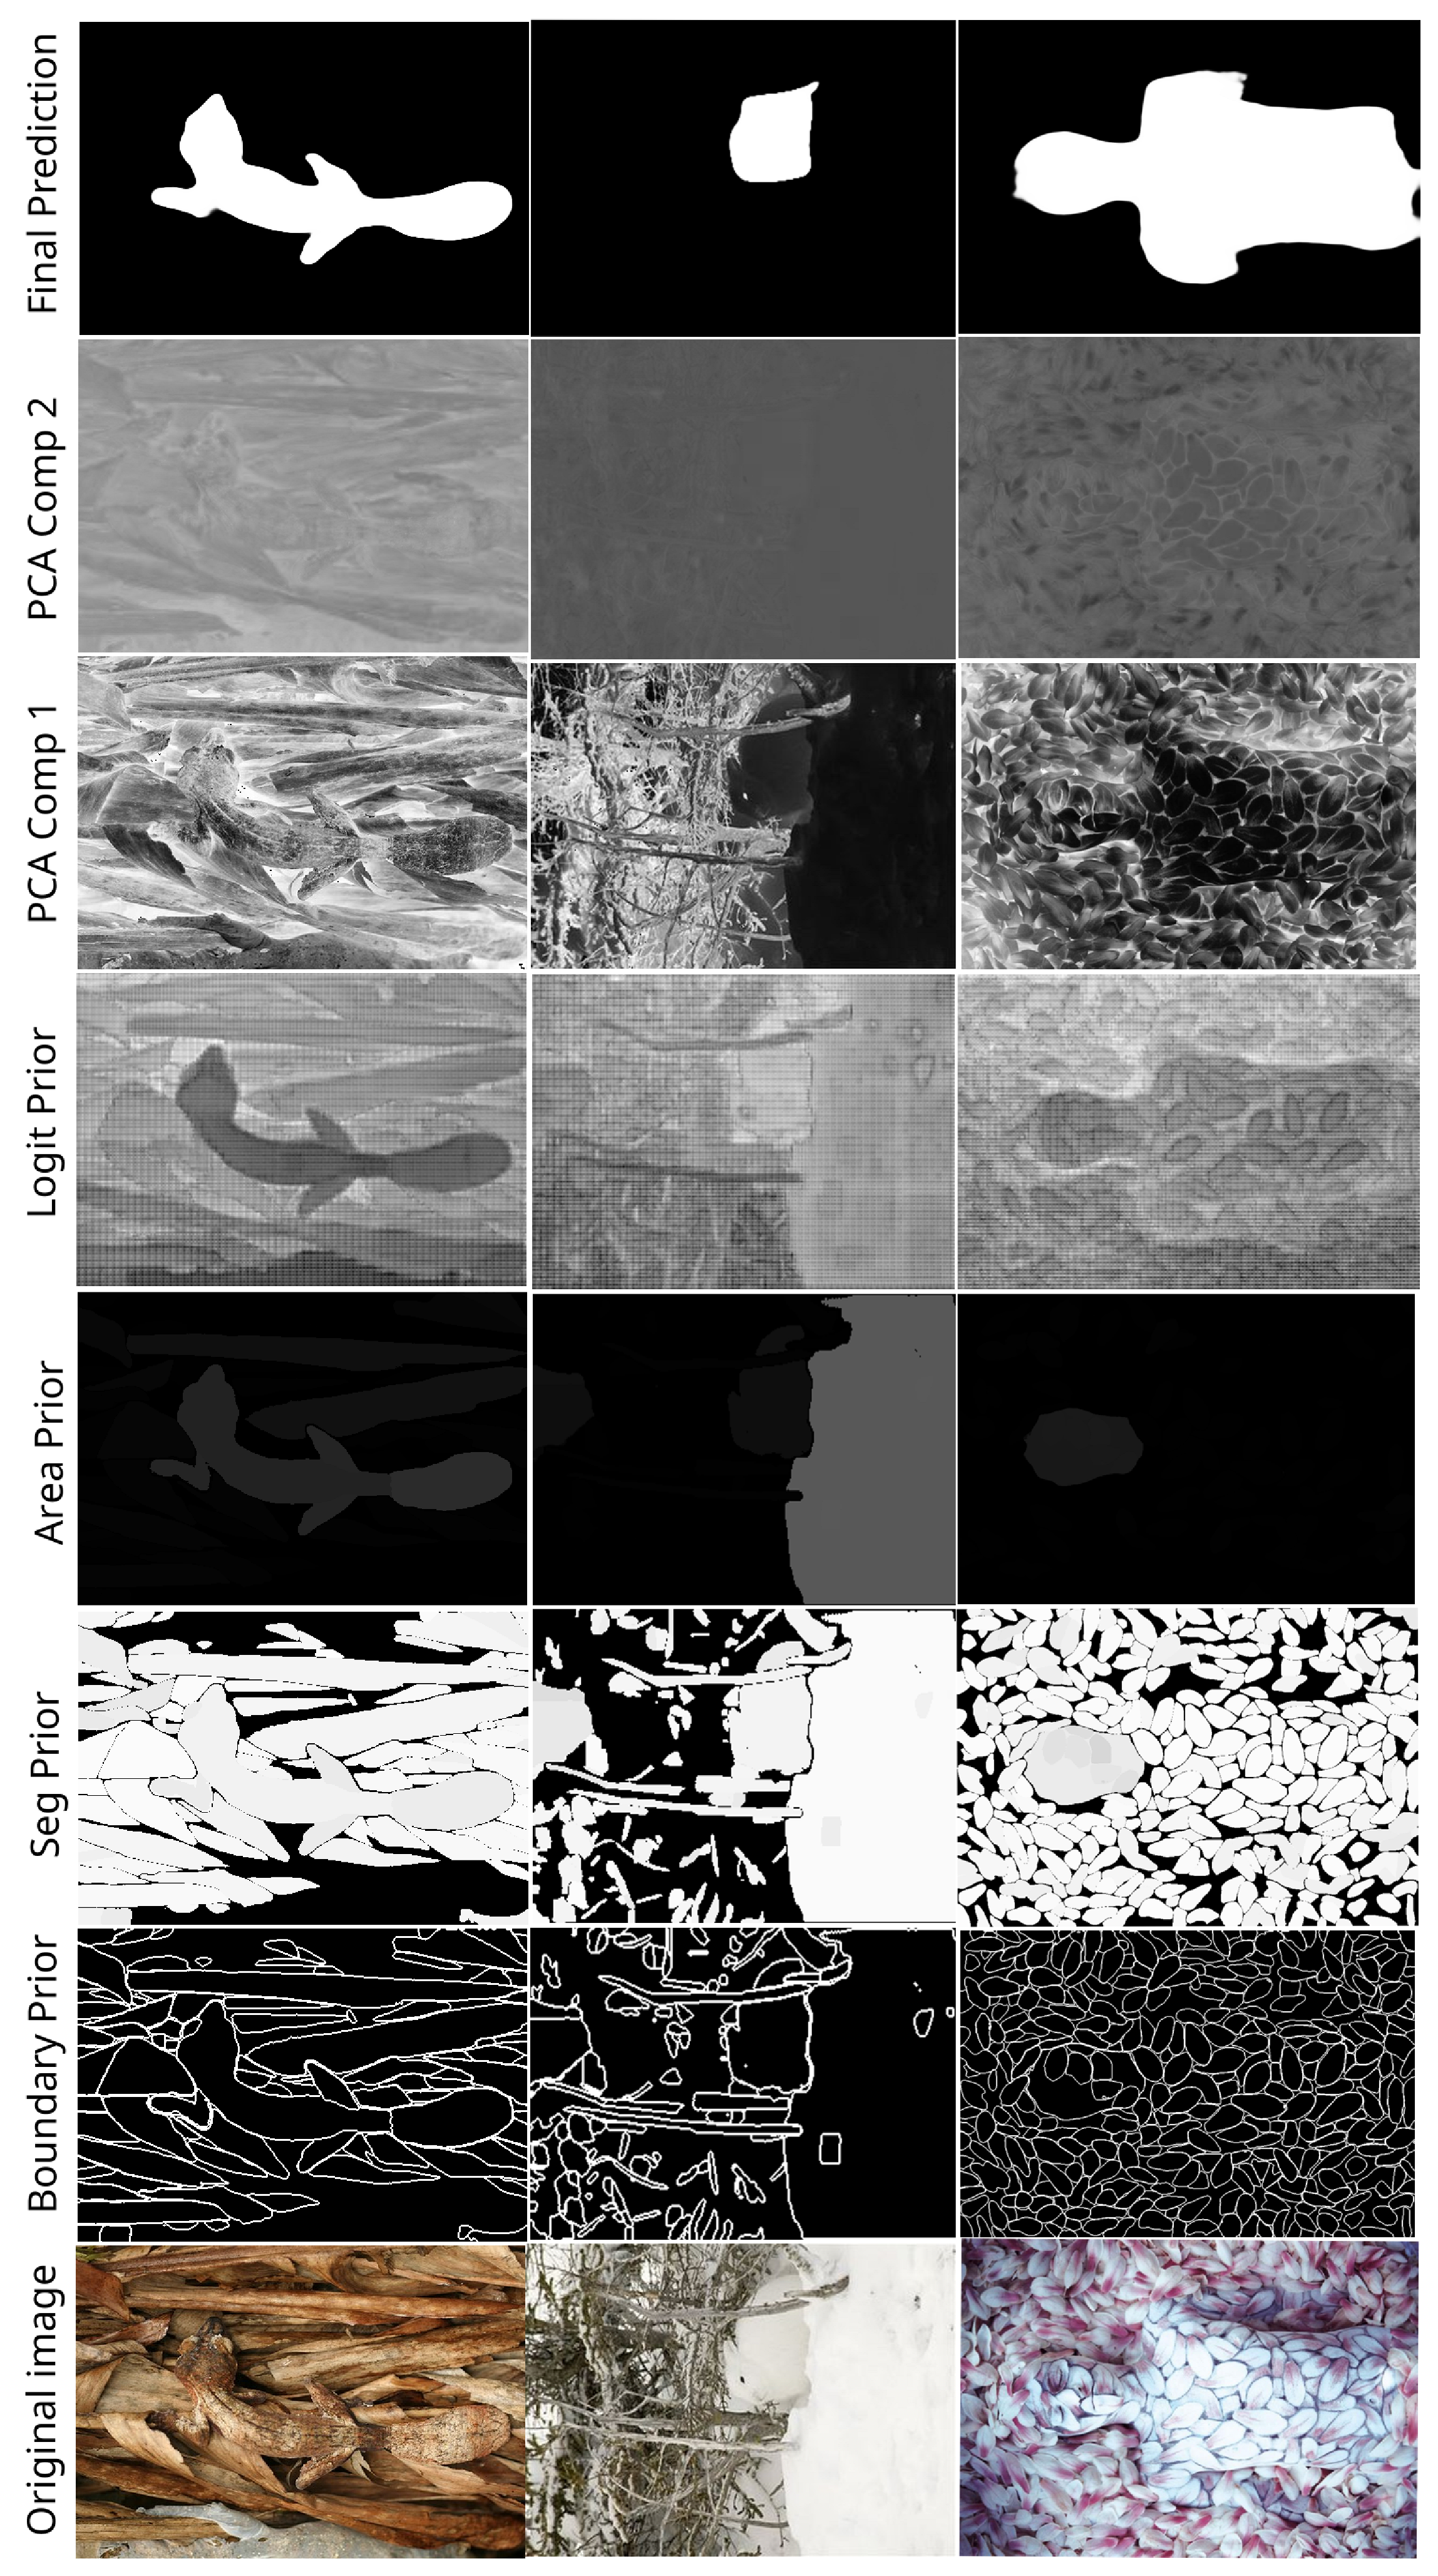

Appendix B. Channel Visual Comparison

2.3.5. PCA-segPrior

- Segmentation Mask Generation: The algorithm begins by generating segmentation masks using a mask generator. These masks represent regions of interest within the image, and each mask is associated with a stability score, which indicates the confidence in the mask’s correctness.

- Segmentation Prior Calculation: The matrix is initialized as a blank matrix (zeros). Then, for each segmentation mask, the algorithm updates . This update involves multiplying each mask by its corresponding stability score and accumulating the results. The segmentation prior thus reflects the confidence in various regions of the image based on the available segmentation masks.

- Dimensionality Reduction via PCA: The image is subject to PCA to reduce its dimensionality from three channels (RGB) to two channels. The reduced representation captures the key features of the image in fewer dimensions, making it more efficient for further processing.

- Scaling of PCA and Segmentation Data: The PCA output and the segmentation prior are normalized to the range to ensure that the data are properly adjusted for visualization and processing.

- Image Reconstruction: The image is reconstructed by combining the scaled PCA results and the segmentation prior into the red, green, and blue channels of the image. The red and green channels come from the PCA output, while the blue channel is influenced by the segmentation prior. This modified image now encodes both the reduced-dimensional representation of the image and additional information from the segmentation.

2.3. Input Augmentation

2.3.1. SAMAug

- the first channel contains the grayscale version of x;

- the second channel is populated with the segmentation prior map, providing additional segmentation-related information;

- the third channel accommodates the boundary prior map, enriching the image with boundary details.

2.3.4. SV-segPrior

- Input Image Preparation: The input image is converted to floating-point format to prepare it for processing. This ensures the compatibility of the pixel values with subsequent operations.

- Segmentation Prior Generation: Using the segmentation masks generated by the SAM model, a semantic prior map is created. For each mask, the segmentation region is weighted by its stability score, and these weights are accumulated across all masks to produce the segmentation prior.

- Color Space Conversion: The image is converted from RGB to HSV color space. This transformation separates the image into hue (H), saturation (S), and brightness (V) channels, allowing for isolated modifications to the hue channel.

- Channel Separation and Modification: The segmentation prior is assigned to the H channel, effectively encoding the semantic information in the hue component of the HSV image. The S and V channels remain unchanged.

- Image Reconstruction: The modified H channel is recombined with the original S and V channels to reconstruct the modified HSV image. The resulting image integrates semantic information directly into its color representation.

2.3.3. RG-logits

- Input Image Preparation: The algorithm starts by setting the input image to the SAM model, preparing it for segmentation prediction. This allows the model to process the image and generate relevant outputs, such as the segmentation mask and the corresponding logits.

- Segmentation Logit Prediction: The SAM model returns the predicted mask along with its associated logits. These logits represent the model’s confidence in different regions of the image, highlighting areas where specific features or objects are present.

- Channel Separation: The image is separated into its red, green, and blue channels. The red and green channels are retained as is; the blue channel is modified based on the segmentation logits (Step 5).

- Logit Normalization: The logits are normalized to fit within the standard image channel range of [0, 255]. This ensures that the logits can be represented as valid pixel values and applied to the blue channel of the image.

- Blue Channel Replacement: The normalized logits replace the original blue channel of the image, resulting in a new image in which the blue channel now reflects the segmentation information. This modification highlights the areas of interest determined by the segmentation model.

- Image Reconstruction: The image is reconstructed by combining the unchanged red and green channels with the modified blue channel. The resulting image now displays the segmentation information while maintaining the original color integrity.